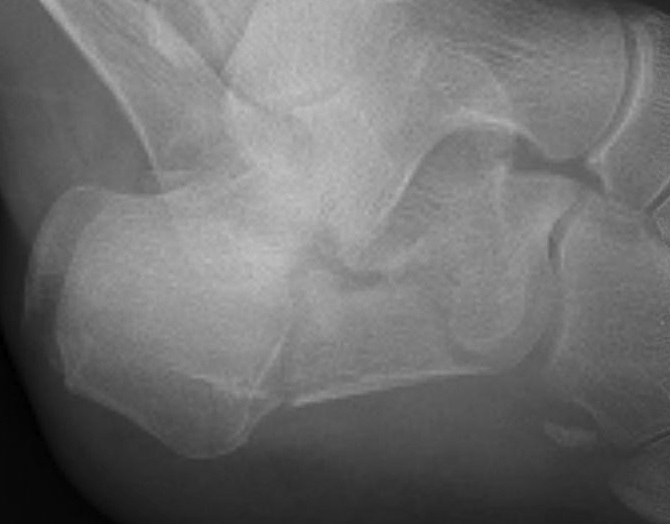

X-ray Views

| Lateral | Oblique view |

|---|---|

|

Bohler's angle Crucial angle of Guisane |

Calcaneocuboid joint |

Xray Angles

Bohler's angle (20-40°)

Lateral xray

Highest point anterior process - highest point on posterior facet - highest point on tuberosity

- represents the height of the calcaneus

- normal 20-40°

Angle of </=0° is associated with a poor outcome

Normal Bohler's angle

Calcaneal fracture with Bohler's angle < 0

Crucial Angle Gissane (120-140°)

Lateral xray

Posterior facet of calcaneum - anterior process of calcaneum

Normal angle of Gissane

Reduced angle of Gissane after fracture